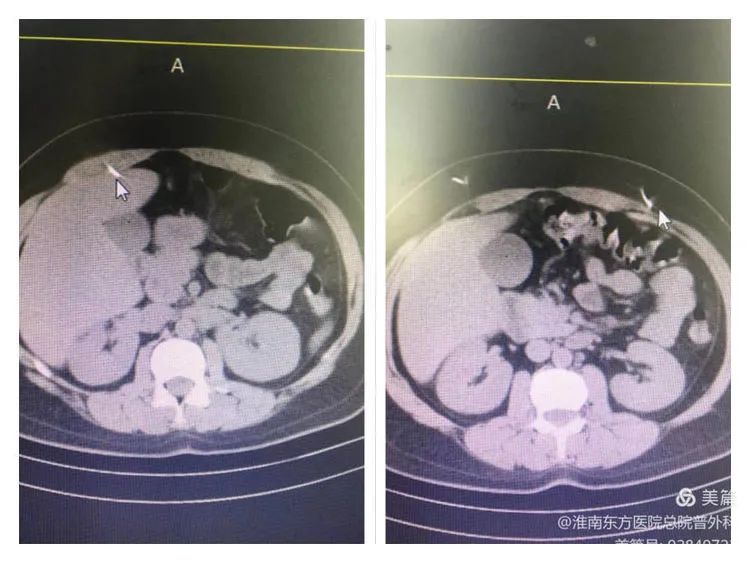

患者入院时完善CT提示,右侧腹部部分金属针刺入肝脏,左侧腹部金属针全部位于腹壁内。

众所周知,肝脏血管丰富且组织质地较为脆弱。这样一根总长约4-5cm的金属针刺入肝脏,患者活动时稍有不慎,很容易划伤肝脏导致大出血。再者,金属针刺入的过程,有没有穿透其他重要的血管、脏器,从CT上无法获得全部信息。病情紧急,患者随时面临着出血休克甚至死亡的风险。公安监管病区医生查阅CT后立即向总院普外科发出紧急会诊申请。总院普外科住院总刘明亮前往会诊后,拟诊“腹部金属异物、消化道金属异物”收入肝胆外科,并立即向普外科副主任张军汇报病人情况。张主任当即召集全科医师参与病例讨论,通过讨论,大家了解了患者本次就诊的整体情况,基本确定了手术人员、手术方式、入路选择、术中注意事项以及相关术后并发症的预防措施。